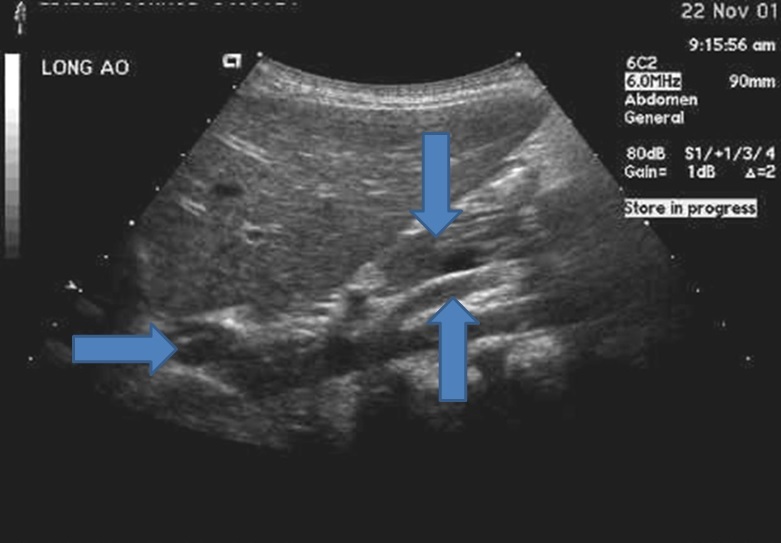

Q

From top down what is the structures?

A

This image is the pancreas is sag view

1. Pancreatic neck

2. SMV

3. Main portal vein it is heading into the liver